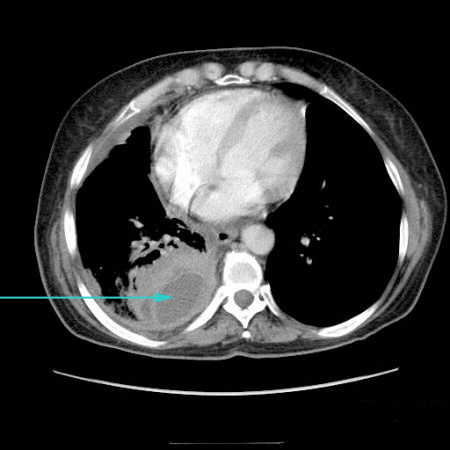

[Figure caption and citation for the preceding image starts]: CT scan showing large right pleural effusionFrom the collection of Dr Nicholas Maskell; used with permission [Citation ends].

CT scan chest may be indicated to assess characteristics of effusions seen on plain chest x-ray (e.g., assess for loculation, pleural rind, empyema). CT may also be used to confirm the diagnosis of pneumothorax if diagnostic uncertainty, as well as diagnosis of mesothelioma and non-mesothelioma malignancy.